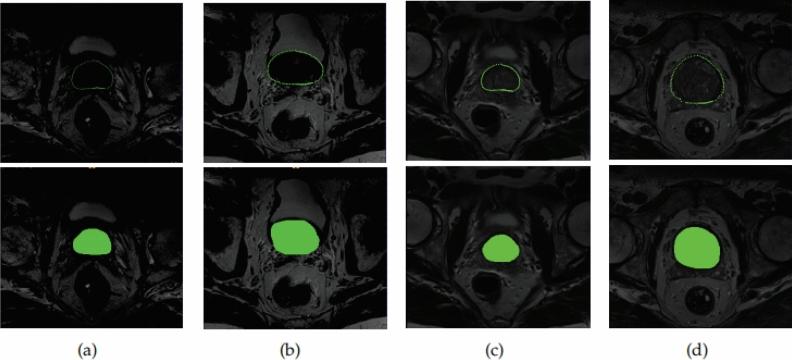

一种语义约束下的前列腺超声图像双向分割方法。

A bi-directional segmentation method for prostate ultrasound images under semantic constraints.

Due to the lack of sufficient labeled data for the prostate and the extensive and complex semantic information in ultrasound images, accurately and quickly segmenting the prostate in transrectal ultrasound (TRUS) images remains a challenging task. In this context, this paper proposes a solution for TRUS image segmentation using an end-to-end bidirectional semantic constraint method, namely the BiSeC model. The experimental results show that compared with classic or popular deep learning methods, this method has better segmentation performance, with the Dice Similarity Coefficient (DSC) of 96.74% and the Intersection over Union (IoU) of 93.71%. Our model achieves a good balance between actual boundaries and noise areas, reducing costs while ensuring the accuracy and speed of segmentation.

摘要

由于前列腺缺乏足够的标注数据,且超声图像中的语义信息广泛而复杂,在经直肠超声(TRUS)图像中准确、快速地分割前列腺仍然是一项具有挑战性的任务。在此背景下,本文提出了一种使用端到端双向语义约束方法的TRUS图像分割解决方案,即BiSeC模型。实验结果表明,与经典或流行的深度学习方法相比,该方法具有更好的分割性能,骰子相似系数(DSC)为96.74%,交并比(IoU)为93.71%。我们的模型在实际边界和噪声区域之间实现了良好的平衡,在确保分割准确性和速度的同时降低了成本。